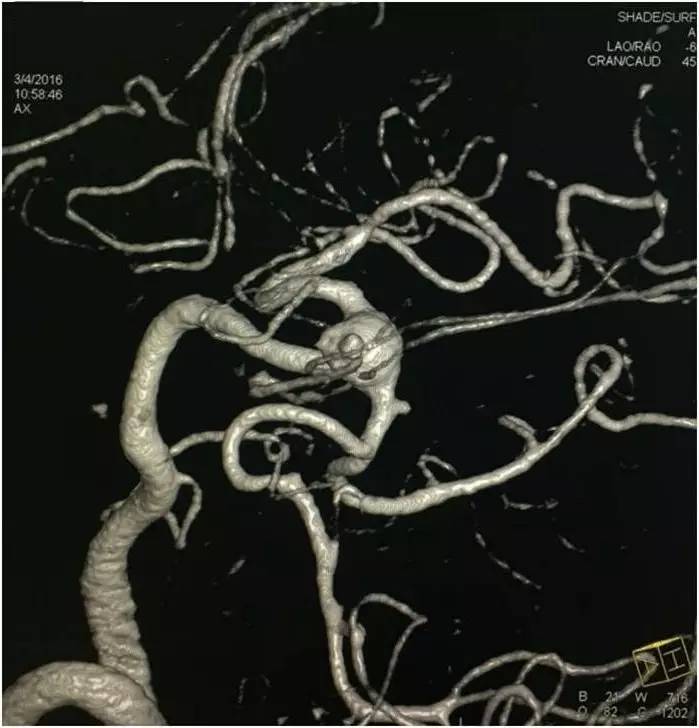

▼左椎动脉造影三维重建,这个角度可以窥清基底动脉顶端动脉瘤和左小脑上动脉瘤,可见基底动脉顶端动脉瘤顶端的子瘤,考虑是SAH的责任动脉瘤。

▼这个角度可以看到左PCA P1段的微小动脉瘤